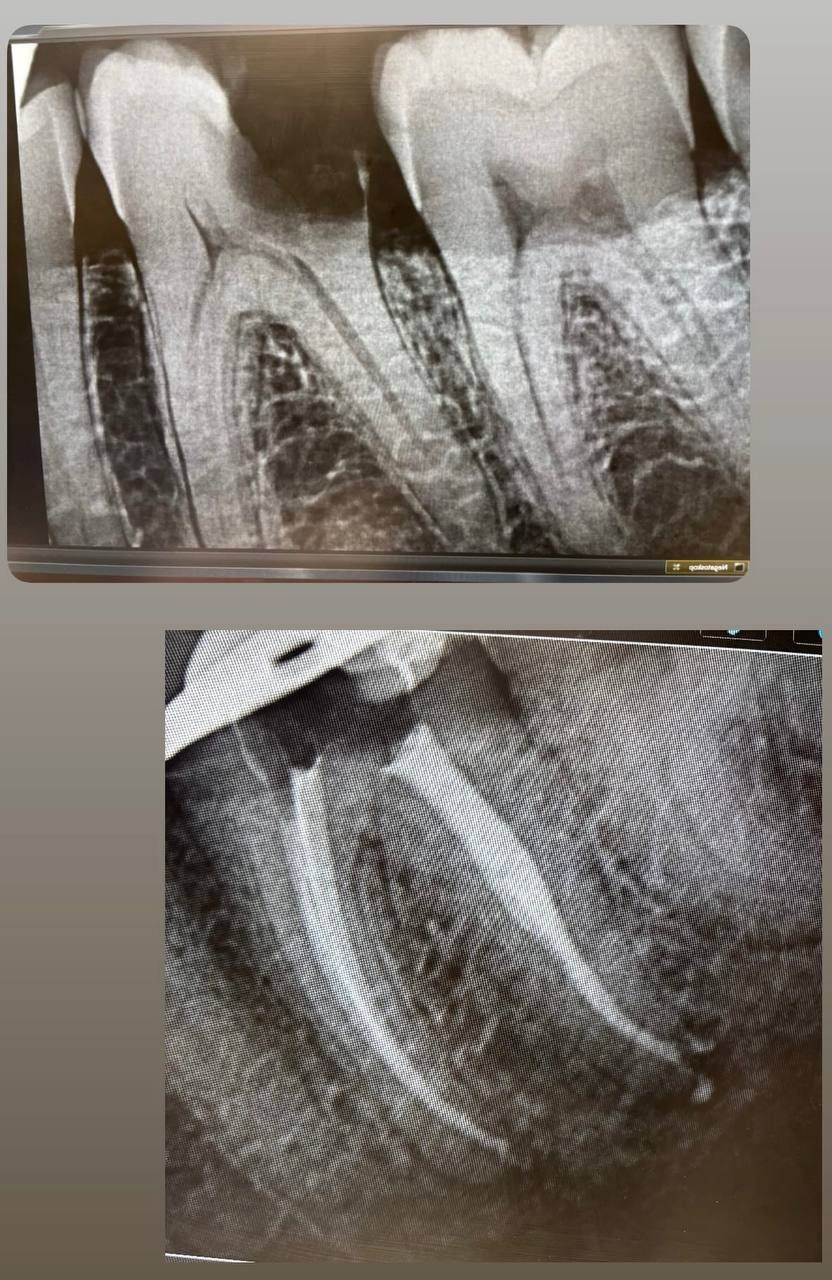

Jestem lekarzem dentystą zajmującym się stomatologią zachowawczą oraz leczeniem kanałowym pod mikroskopem (endodoncja mikroskopowa). W swojej pracy stawiam na kompleksowe podejście do zdrowia jamy ustnej – dokładną diagnostykę, skuteczne leczenie oraz profilaktykę.

Specjalizuję się w leczeniu próchnicy, odbudowie zębów oraz leczeniu kanałowym, w tym leczeniu kanałowym pod mikroskopem, które pozwala na bardzo precyzyjne oczyszczenie i opracowanie kanałów korzeniowych. Dzięki zastosowaniu mikroskopu możliwe jest skuteczne leczenie nawet bardziej skomplikowanych przypadków oraz powtórne leczenie kanałowe (reendo).